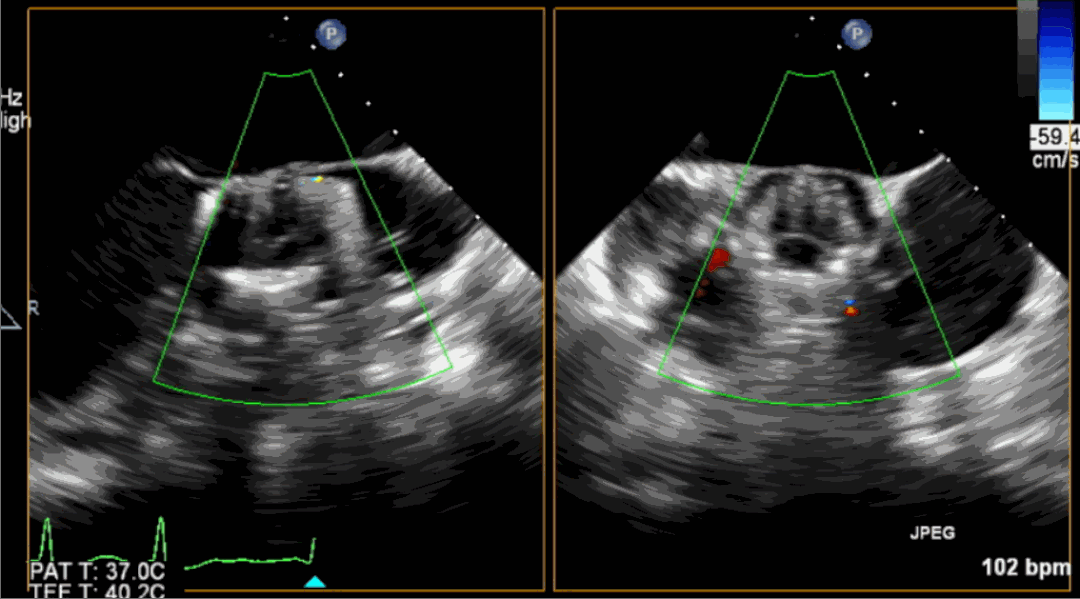

術后超聲影像圖

手術采用經心尖入路,對患者進行全麻后,在左側心尖處做3-4cm微創手術切口,在DSA及超聲引導下手術順利完成。從導入器械到完成瓣膜置入,僅耗時約10分鐘。術后即刻主動脈瓣返流程度由術前大量返流轉為消失,患者于導管室拔除氣管插管,次日由ICU轉入普通病房。